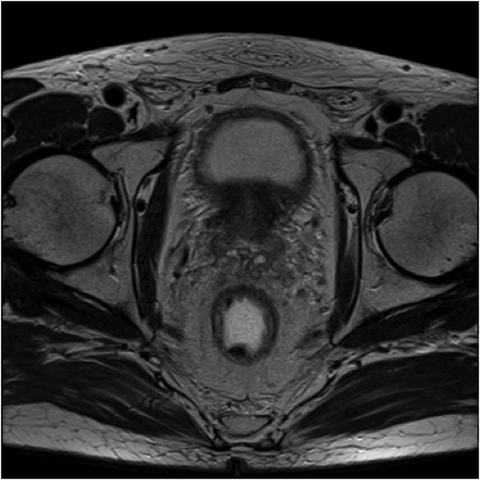

Fig1. Pacient cu neoplasm rectal stadiul IIIC (T3; N2; M0) confirmat bioptic, adenocarcinom mixt G2

a-d imagini T2 ponderate în plan sagital, oblic axial și oblic coronal – masă tisulară dezvoltată superior de joncțiunea anorectală, lateral dreapta, cu minimă extensie la nivelul grăsimii mezorectale și limfoganglioni mezorectali cu diametru de până la 10 mm;

e,f) restricție de difuzie la nivelul tumorii rectale și a doi ganglioni mezorectali

g,h,i) priză de contrast moderată la nivelul tumorii rectale și al ganglionilor mezorectali

j) reconstrucții curbe în planul adevărat al rectului, cu evidențiere mai bună a fasciei mezorectale